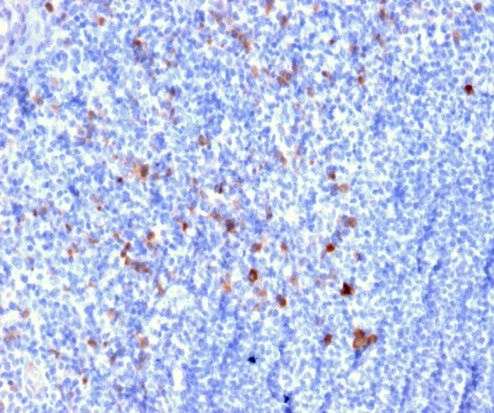

CD25/IL2RA (Activated Lymphocyte Marker) Monoclonal Antibody (IL2RA/2394)

CD25 (IL2 receptor alpha chain/IL2RA) is a cytokine that plays a role in the proliferation of T and B lymphocytes. The receptor of this cytokine (IL2RA) is a heterotrimeric protein complex with a gamma chain also shared by interleukin 4 (IL4) and interleukin 7 (IL7). IL2RA, IL2R beta chain (IL2RB), and the IL2R gamma chain (IL2RG), constitute the high-affinity IL2 receptor. Homodimeric IL2RA chains result in low-affinity receptor, while homodimeric IL2RB chains produce a medium-affinity receptor. The expression of IL2 in mature thymocytes is monoallelic, which represents an unusual regulatory mode for controlling the precise expression of a single gene. IL2 is primarily produced by mature T cells. IL2 plays an important role as a growth factor, differentiation factor, and regulator of cell death. IL-2 stimulates the proliferation of B cells, augments natural killer cell activity, and inhibits granulocyte macrophage colony formation. The targeted disruption of a similar gene in mice leads to ulcerative colitis-like disease, which suggests a role in the immune response to antigenic stimuli. Mutations in this gene are associated with interleukin 2 receptor alpha deficiency.